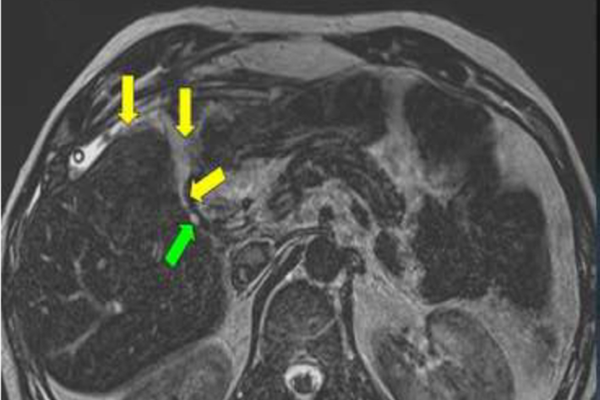

Endoscopic Retrograde Cholangiopancreatography (ERCP) is a specialized procedure used to diagnose and treat conditions affecting the bile ducts, gallbladder, pancreas, and liver. It combines endoscopy and fluoroscopy to visualize the ducts, identify blockages or abnormalities, and treat them in the same session.

Diagnostic Evaluation

X-rays help the doctor identify stones, strictures, or tumors in the ducts.

Gallstones in the Bile Duct

Removes stones blocking the bile flow and causing pain or infection.

Pancreatic or Bile Duct Tumors

Helps in identifying growths or narrowing affecting digestion and bile flow.